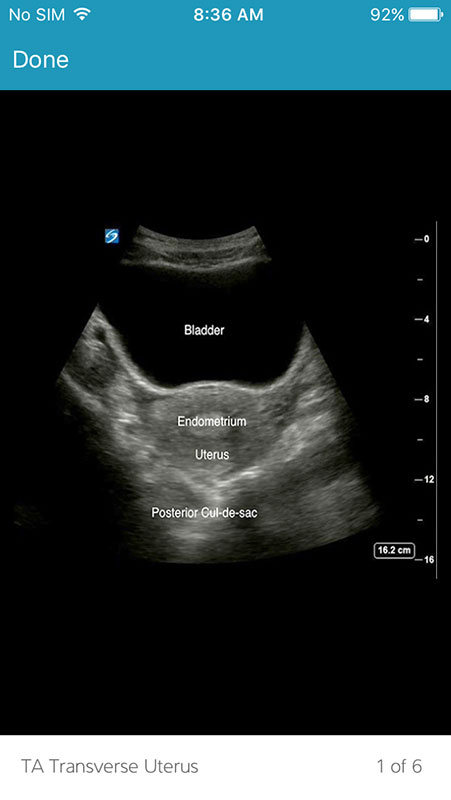

The Images section contains still images of ultrasound scans showing different anatomic systems, with or without labels. Images have no textual descriptions or narration tho.

However, I've encountered a problem here. Even after I downloaded a set of images, they weren't available after I've opened them. For example, ultrasound for 1st Trimester Pregnancy contains 19 images. I was able to open only two, while the rest of the images couldn't open, showing generic image icon.